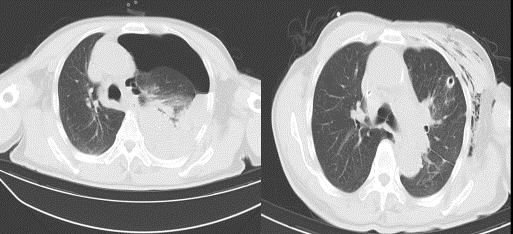

患者于某某,6月15日凌晨04时急诊入院,胸部CT提示左侧大量液气胸,左肺被压缩约80%,纵隔受压右偏。询问病史,否认外伤史,只是在入院前一天咳嗽后突发胸痛伴呼吸困难。值班医生付东林紧急行床旁胸腔闭式引流术,引流出大量气体及血性液体约1500ml,心胸外科副主任马广耀组织科室团队成员紧急进行讨论后,一致决定积极完善术前准备,急诊全麻下行胸腔镜探查术。

术中发现患者胸膜顶两处活动性出血,胸腔大量积血及血凝块,共吸出约800ml积血,争分夺秒下彻底止血,切除病变肺大疱并彻底止血后未见有活动性出血,同时行胸腔镜下胸膜固定术预防术后复发。术后患者在科室医护人员的指导下早期进行呼吸功能锻炼,现恢复良好,择期康复出院。